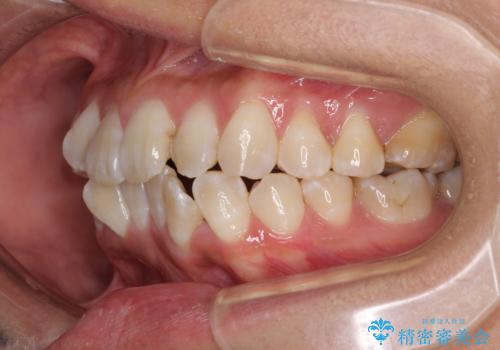

全く目立たないワイヤー矯正 上下裏側矯正

- 上下の前歯のでこぼこを気にして来院された患者様です。

職場の都合により、表側のワイヤー装置や着脱作業が頻繁なマウスピース矯正は困難とのことで、全く目立たない裏側矯正装置を用いて口元を整えることとしました。

途中転勤や出産があり、通院できない期間が長くありましたが、無事に歯列を整えることができました。